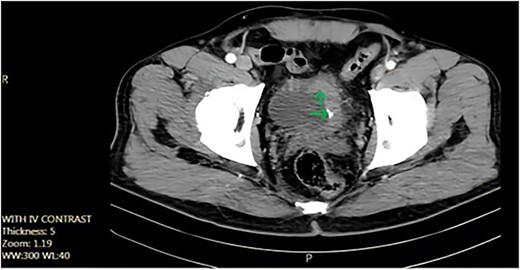

We report the case of a 52-year-old non-smoker, non-addicted male with a past surgical history of cystolithotomy 30 years ago and no comorbidities. The patient presented to our center with painless gross hematuria without any obstructive or irritative urinary signs or symptoms. Initial ultrasonography revealed an 18 × 9 mm bladder stone, for which the patient was referred for cystolitholapaxy. Subsequent follow-up with ultrasonography and abdominopelvic computed tomography (CT) scan identified a 45 × 25 mm triangle laminated bladder stone (Fig. 1).

Axial pelvic CT scan shows large urinary bladder tumor (arrow).

During cystoscopy, a large mass was observed in the bladder. Subsequently, transurethral resection of the bladder tumor was performed. The pathology report indicated high-grade urothelial cell carcinoma with lamina propria involvement. Chest and abdominopelvic CT scans and bone scans revealed no distant metastasis. The patient underwent neoadjuvant chemotherapy (four cycles of etoposide and cisplatin with etoposide 100 mg/m2 daily for 5 days and cisplatin 20 mg/m2 daily for 5 days administered every 3 weeks), which proved ineffective. Consequently, a radical cystoprostatectomy with orthotopic neobladder urinary diversion and pelvic lymphadenectomy was performed.